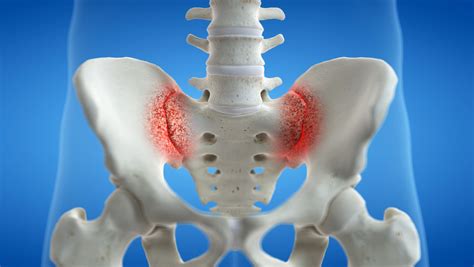

Understanding the Sacroiliac Joint and Why Dysfunction Occurs

The sacroiliac joints are the two joints connecting your sacrum (the triangular bone at the bottom of your spine) to your ilium (the large pelvic bones on either side). Unlike the highly mobile joints in your knees or elbows, the SI joints are designed to provide stability rather than a wide range of motion. Their primary role is to act as shock absorbers between the upper body and the legs.

When these joints become inflamed or move abnormally—a condition known as SI joint dysfunction—it can cause significant discomfort. This pain is often felt in the lower back, buttocks, and sometimes down the back of the thighs. Several factors can lead to this dysfunction, including: